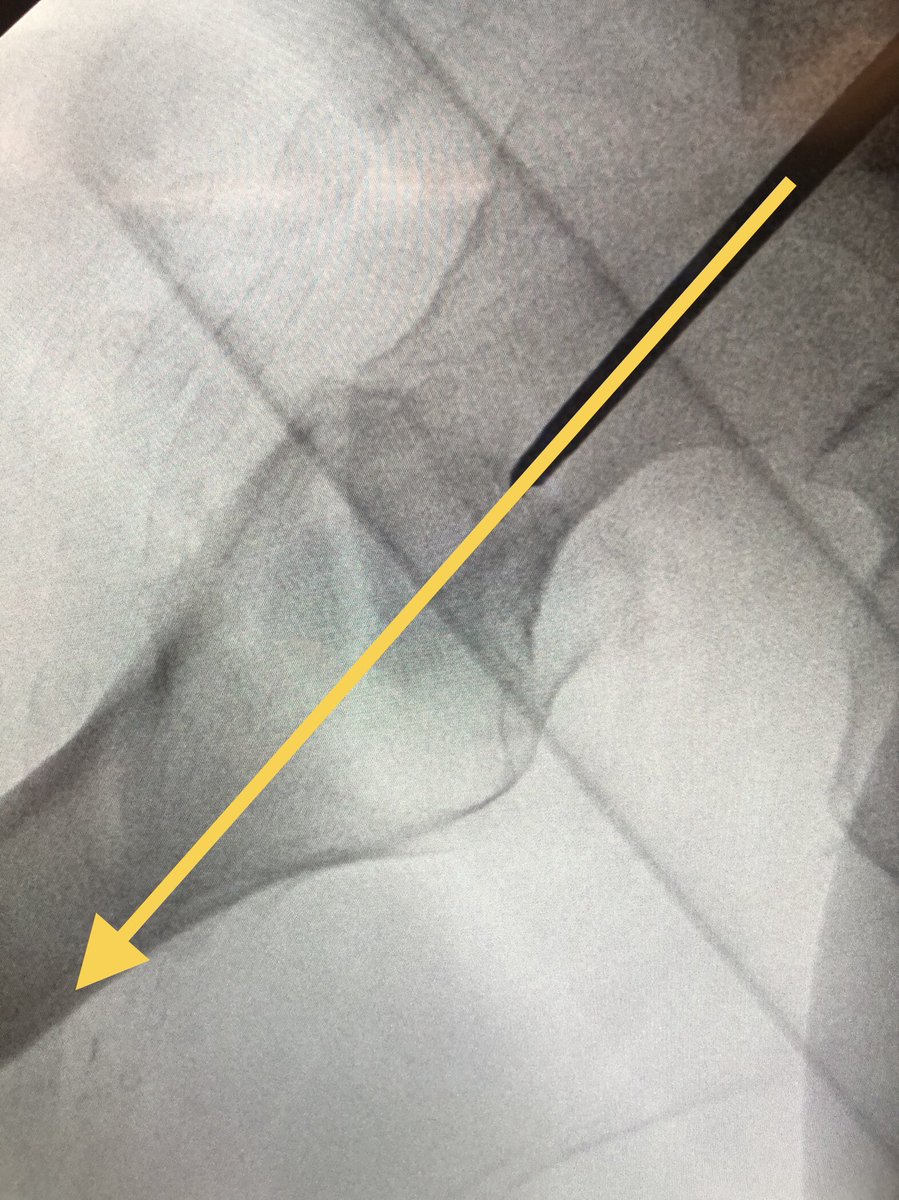

[4/18] The correct amount of traction, if you don’t want to judge by the other side, is usually close when greater trochanter lines up w/center of femoral head (yellow). You can play around with it and see how it looks. Can also always clamp if traction alone isn’t good enough.

[15/18] I always try to build in some compression. The place to watch is the inferior medial portion of the fracture (arrow). Don’t overdo it or the nail starts to migrate medially.

[18/18] The troch fragment is little abducted here, I don’t worry so much about screw being close to fracture line because nails don’t rely on lateral wall to work. Keep TAD (or calTAD as I do) small and most ITs heal without an issue. I also don’t use blades. Thanks for reading!